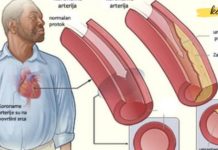

High blood pressure (also known as hypertension) is a widespread health issue that affects millions of people around the world. Often called the “silent killer,” it typically has no obvious symptoms, yet it can lead to serious complications like heart attacks, strokes, kidney failure, and other life-threatening conditions if left untreated. While prescription medications are commonly used to manage hypertension, many people seek natural ways to reduce blood pressure—either as a complementary approach or as a preventive measure.

When any of these systems are out of balance, your heart may have to work harder to pump blood, leading to elevated pressure in the arteries. Over time, this strains the heart and damages blood vessels.

🍈 2. Guava: Balancing Cholesterol and Pressure

This tropical fruit may not be in everyone’s fridge, but it should be. Guava is an excellent natural remedy for both lowering blood pressure and improving cholesterol balance.

It works by:

Reducing levels of LDL (bad cholesterol)

Increasing HDL (good cholesterol)

Providing antioxidants that protect your heart and arteries

A study published in a nutrition journal found that people who consumed guava regularly experienced significant improvements in their blood pressure and lipid profiles.

Combat cholesterol buildup

🥕 9. Carrots: Heart-Healthy and Anti-Inflammatory

Carrots offer a wide range of health benefits, particularly due to their high content of:

Beta-carotene

Vitamin C

Antioxidants

These nutrients help lower cholesterol levels, protect arterial walls, and reduce the risk of plaque buildup in the arteries. Drinking fresh carrot juice or adding raw carrots to salads can support heart health naturally.